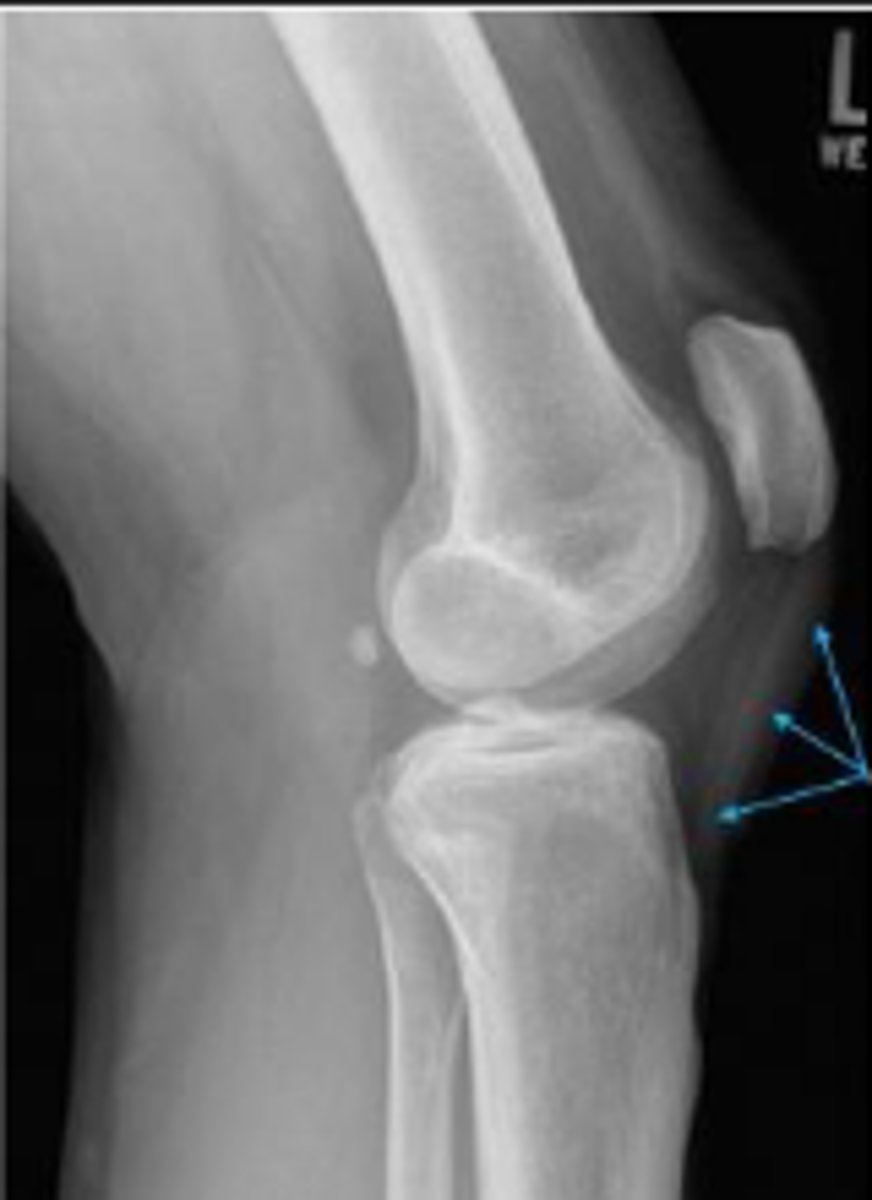

Lipohemarthrosis

What are the arrows pointing to?

Cross table lateral of the left knee

What does 'x-table' mean?